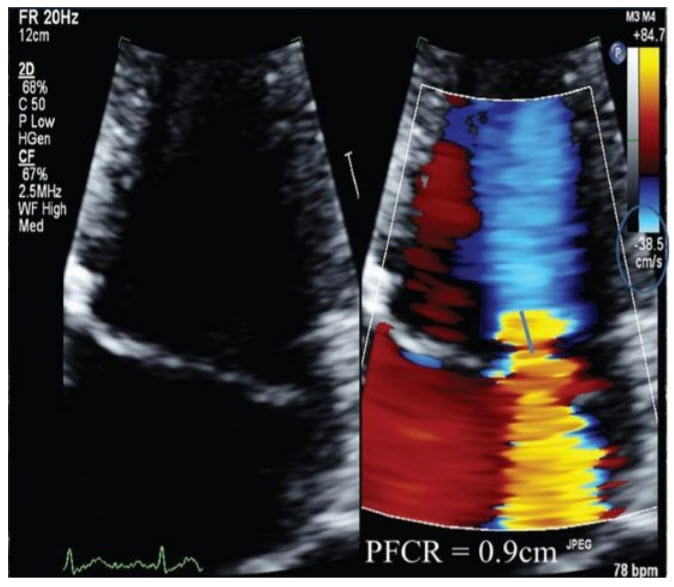

Assuming an aliasing velocity of 40 cm/s and an MR Vmax of 5 m/s, based on the PFCR seen here, what is the estimated effective regurgitant orifice area (EROA)?

0.4 cm2 . The EROA based on the assumptions above is 0.4 cm2 consistent with severe MR. The EROA is calculated using the abbreviated proximal isovelocity surface area (PISA) method as r 2 /2 (r = radius of the PFCR). In this case, the radius is 0.9 cm; therefore, the EROA can be estimated as 0.4 cm2.